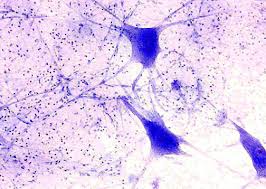

Νευρικός Ιστός

Ο νευρικός ιστός συναντάται αποκλειστικά στο νευρικό σύστημα (κεντρικό και περιφερικό). Τα κύρια κύτταρα του νευρικού ιστού είναι οι νευρώνες. Οι νευρώνες είναι αυτοί που μεταβιβάζουν τα σήματα από το ένα σημείο του σώματος στον εγκέφαλο και αντίστροφα. Στον νευρικό ιστό υπάρχουν και πολλά άλλα κύτταρα των οποίων όμως βασική λειτουργία είναι να προστατεύουν, να μονώνουν και να θρέφουν τους νευρώνες διότι αυτοί είναι οι πιο ευαίσθητοι. Τα κύτταρα αυτά στο κεντρικό σύστημα αποτελούν την μικρογλοία. Μέσα στον εγκέφαλο, τα διάφορα κυτταρικά συστατικά συναθροίζονται σε διαφορετικά σημεία. Για παράδειγμα τα κεντρικά σώματα των νευρώνων συναθροίζονται σε δομές που λέγονται πυρήνες ενώ οι νευρικές ίνες (άξονες και δενδρίτες) στο νευροπίλημα. Ο νευρικός ιστός είναι ο ιστός του οργανισμού που έχει τις μεγαλύτερες ανάγκες σε ενέργεια άρα και σε γλυκόζη σε σχέση με όλους τους άλλους ιστούς. Αυτό γιατί, ο νευρικός ιστός και τα συστήματα που δομεί είναι υπεύθυνος για τις λειτουργίες όλων των άλλων ιστών.